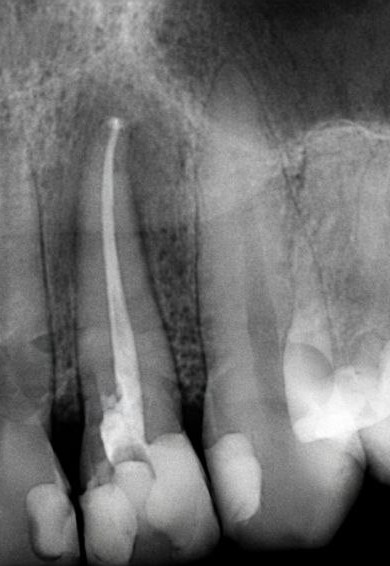

Endodòncia:

L’endodòncia, també coneguda com a tractament de conductes o desvitalització, és el tractament dental de les lesions que afecten la polpa (nervi), ja sigui parcialment o totalment, a causa de càries profundes, fractures, traumatismes o infeccions no tractades.

Aquestes lesions pulpars poden causar dolor agut, sensibilitat al fred o a la calor, dolor en mastegar o canvis en el color de les dents. En alguns casos, poden ser asimptomàtiques, però si hi ha necrosi pulpar (mort del teixit pulpar), poden derivar en inflamació i abscessos (flemó).

L’objectiu de l’endodòncia és alleujar el dolor eliminant la infecció i conservant la dent afectada, evitant-ne l’extracció.

1. Diagnòstic: Es fan radiografies per avaluar el dany a la polpa i el teixit circumdant.

5. Farçit i segellat: Els conductes es farceixen amb un material biocompatible (gutaperxa) per evitar reinfeccions.